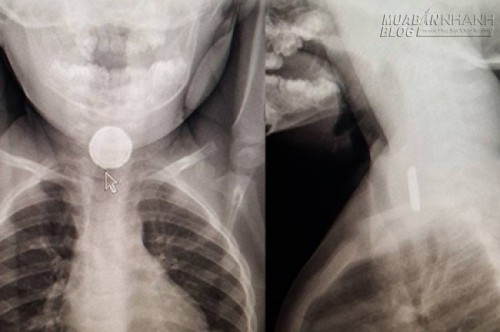

| Hình ảnh X-quang viên pin tròn mắc kẹt trong thực quản (Ảnh: CTV News) |

Tại bác sĩ thứ tư, cha mẹ Katie yêu cầu được cho con chụp X-quang. Kết quả cho thấy có một vật nhỏ mắc kẹt trong thực quản cô bé 2 tuổi.

Khi đó, các bác sĩ phát hiện ra nó đã bắt đầu ăn mòn và làm hỏng thực quản của Katie. Viên pin tròn nhỏ nhanh chóng được lấy ra và may mắn, Katie đã phục hồi tốt sau điều trị.